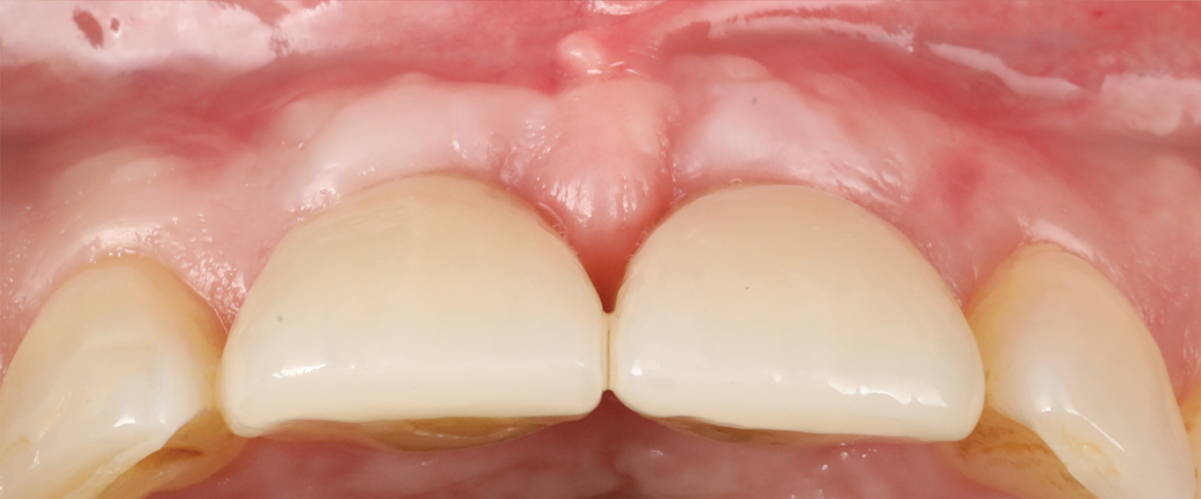

Figure 14 depicts the final outcome at 1 year (which can be compared to the pretreatment photograph in Figure 1). Figure 15 through Figure 18 show clinical comparisons of the outcome at baseline and 1 year, while Figure 19 and Figure 20 provide an ultrasonographic characterization of the soft tissue at baseline and 1 year. The facial probing depths at 1 year were 3-3-3 mm for implant No. 8 and 3-2-3 mm for implant No. 9. The patient was highly satisfied with the esthetic outcomes and overall treatment.

Fig 14. Final outcome at 1 year.

Figure 14